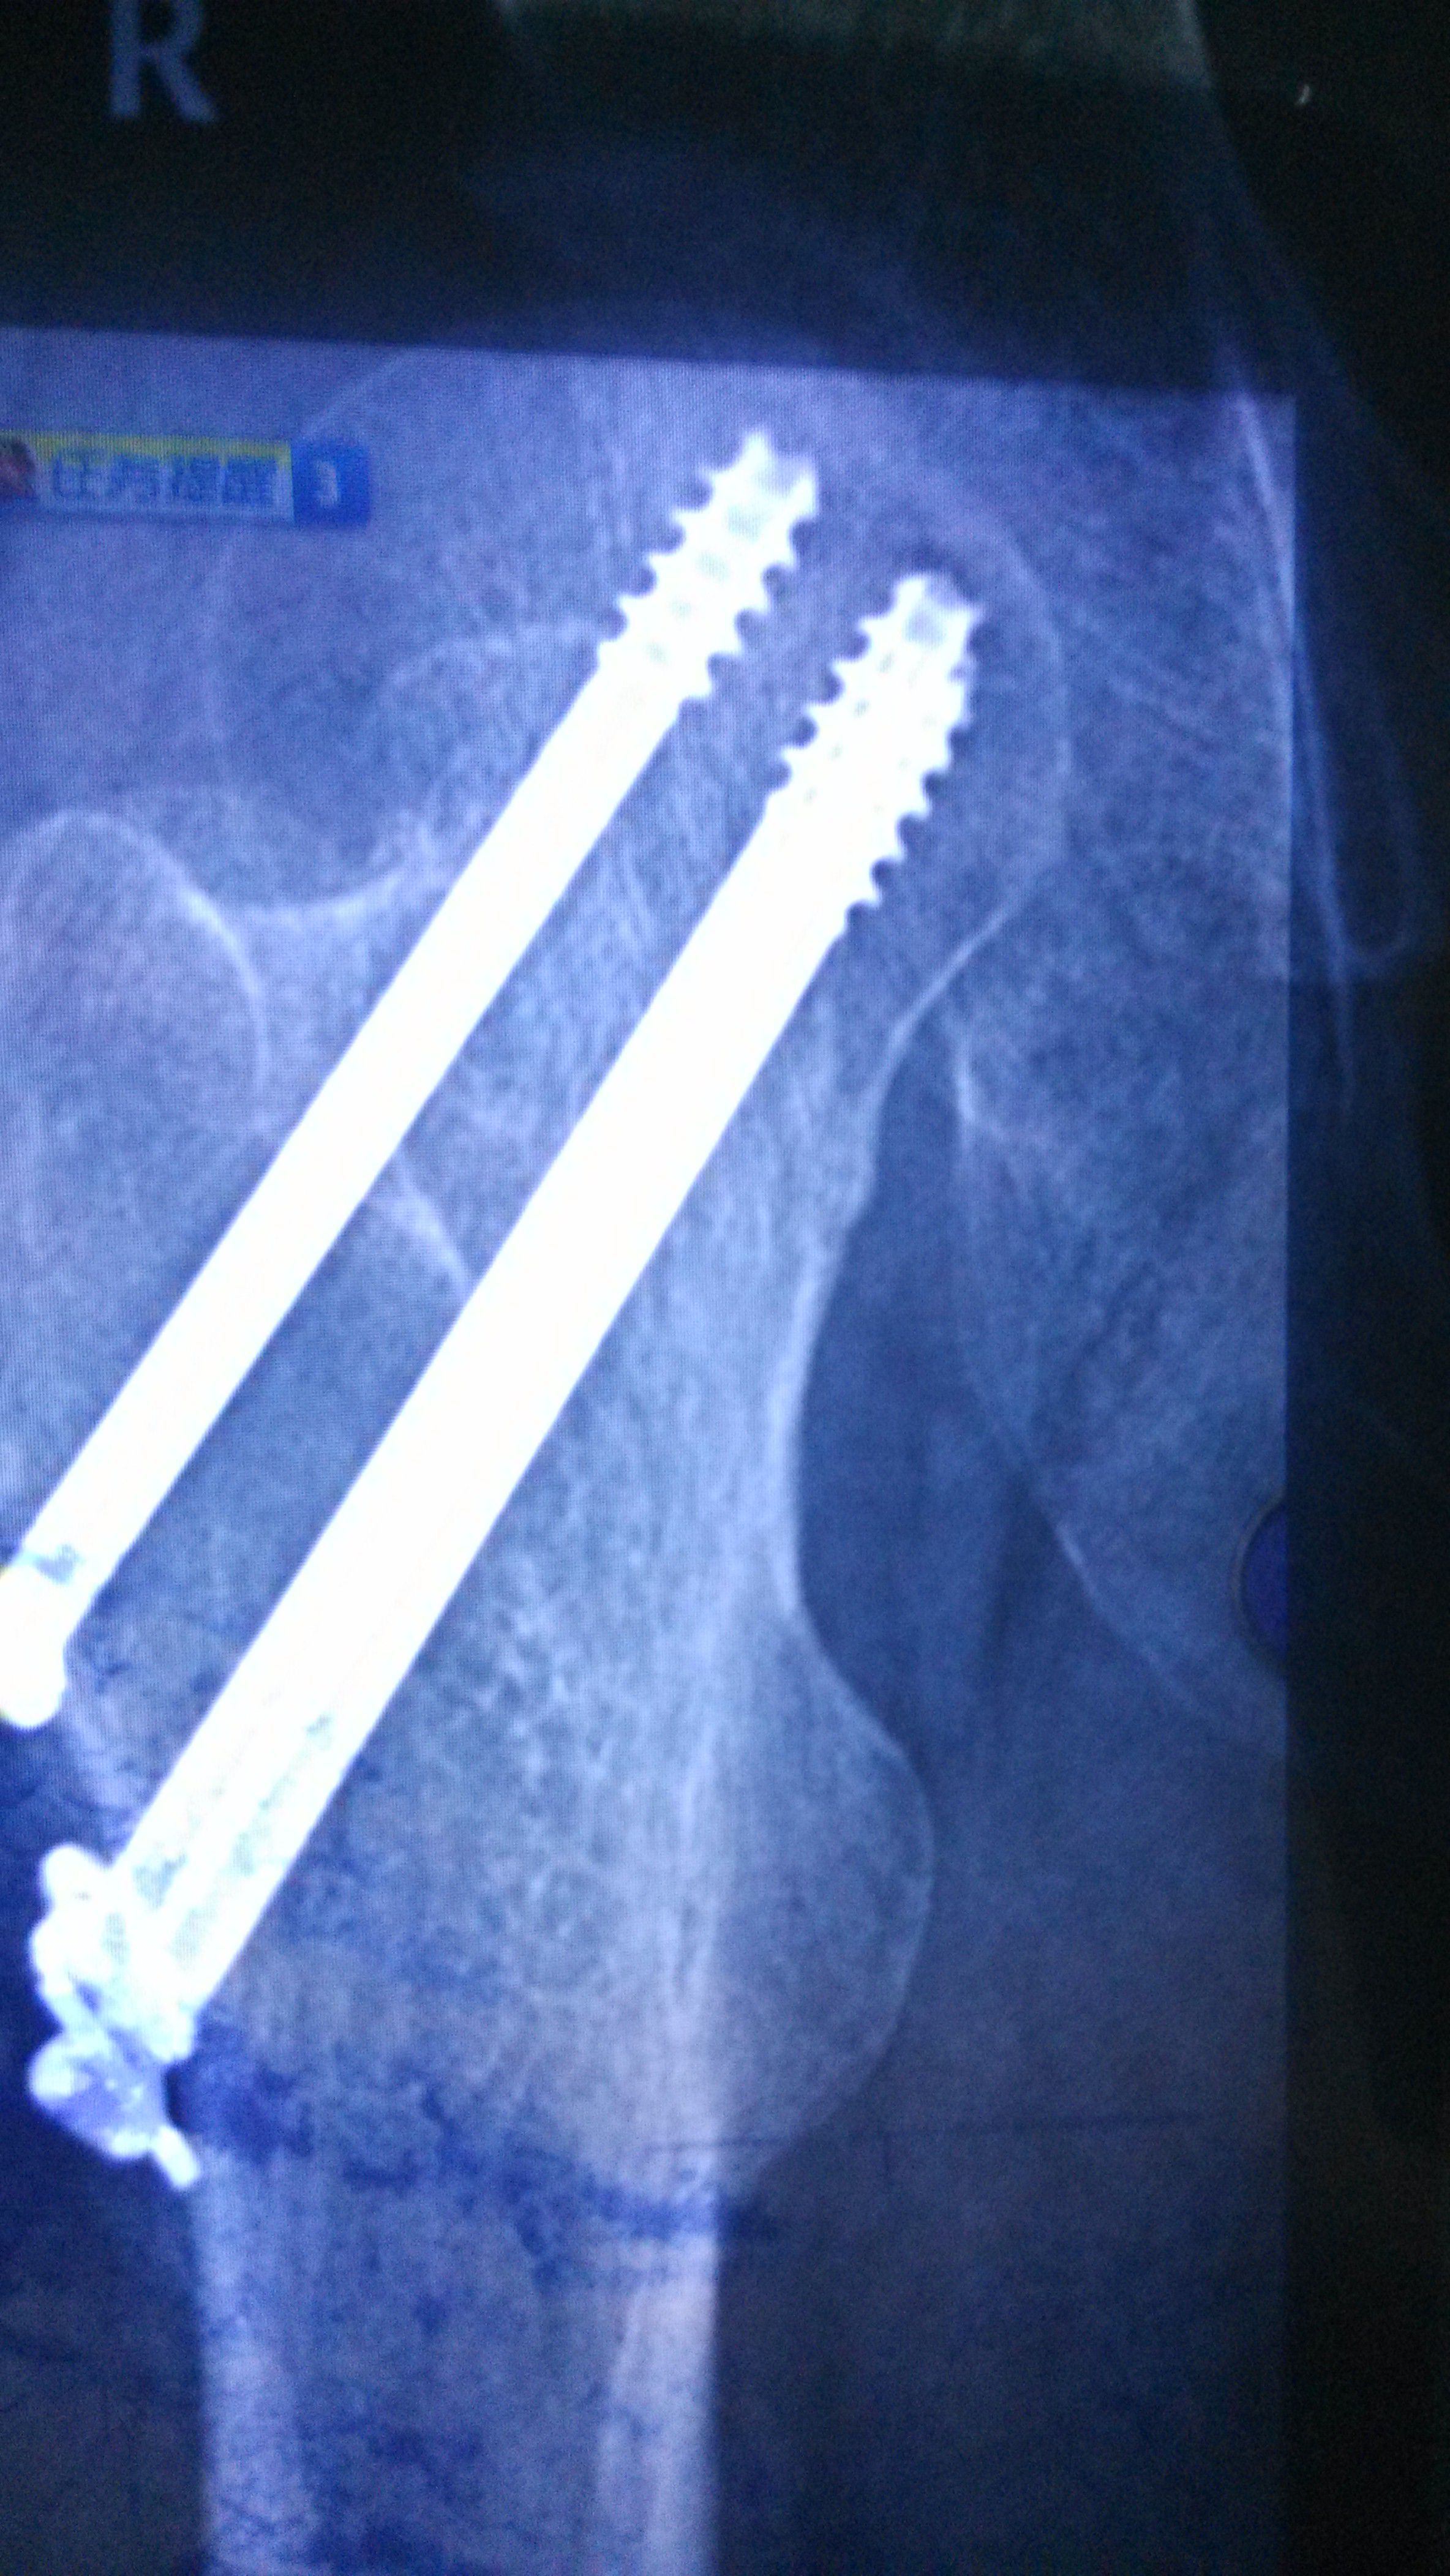

股骨颈骨折内固定七个月了,麻烦教授给看看~能不能够骑单车锻炼,谢谢了 点击展开 匿名用户 2015-06-03 21:00 满意回答 你好,股骨颈骨折内固定七个月了洞炼舞,看片队垃上,愈合不错,可糟相以锻炼的。 2015-06-03 21:08 宝宝知道提示您:回答为网友贡献,仅供参考。 相关问题 刚生完宝宝2个月这样能不能骑单车锻炼呐? 我怀孕三四周了,我每天都坚持去健身房跑步,骑单车,每次都要锻炼至少一个小时 吃饭也不忌口 股骨颈骨折七个月,现在医生诊断有坏死可能,请咨询如何进行康复治疗